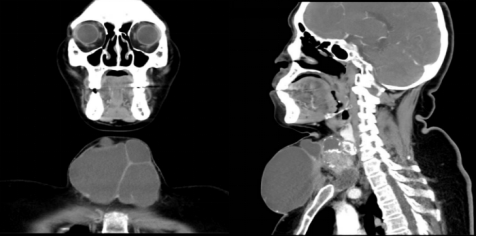

吕阿姨就诊时的术前影像学检查令所有人都捏了一把汗:肿瘤从颈部蔓延到胸壁,范围极其广泛,不仅肿瘤体积巨大,侵犯气管壁、喉返神经及颈内静脉等重要器官;更凶险的是,颈部淋巴结转移灶包裹着颈部重要的血管(颈总动脉、颈内静脉),生命岌岌可危。

▲患者影像学提示肿瘤巨大,从甲状腺区域蔓延到胸壁